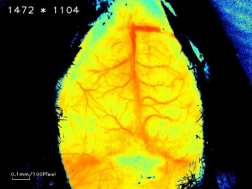

④活体脑部血流监测:激光多普勒或激光散斑成像技术可监测脑部血管血流动态变化,通过卒中前后血管血流的变化可以判断脑部血管梗塞情况(如图2所示),进而可评估模型的成功性以及药物干预的效果。

正常鼠 MCAO鼠

图2:正常组和MCAO模型组小鼠脑部血流成像对比图(佳维斯实验数据)